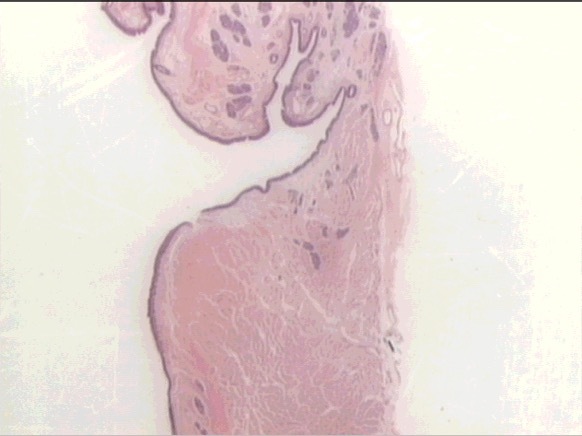

larynx

false vocal cord

true vocal cord

PCCE v. SSEnk

glandular epithelium